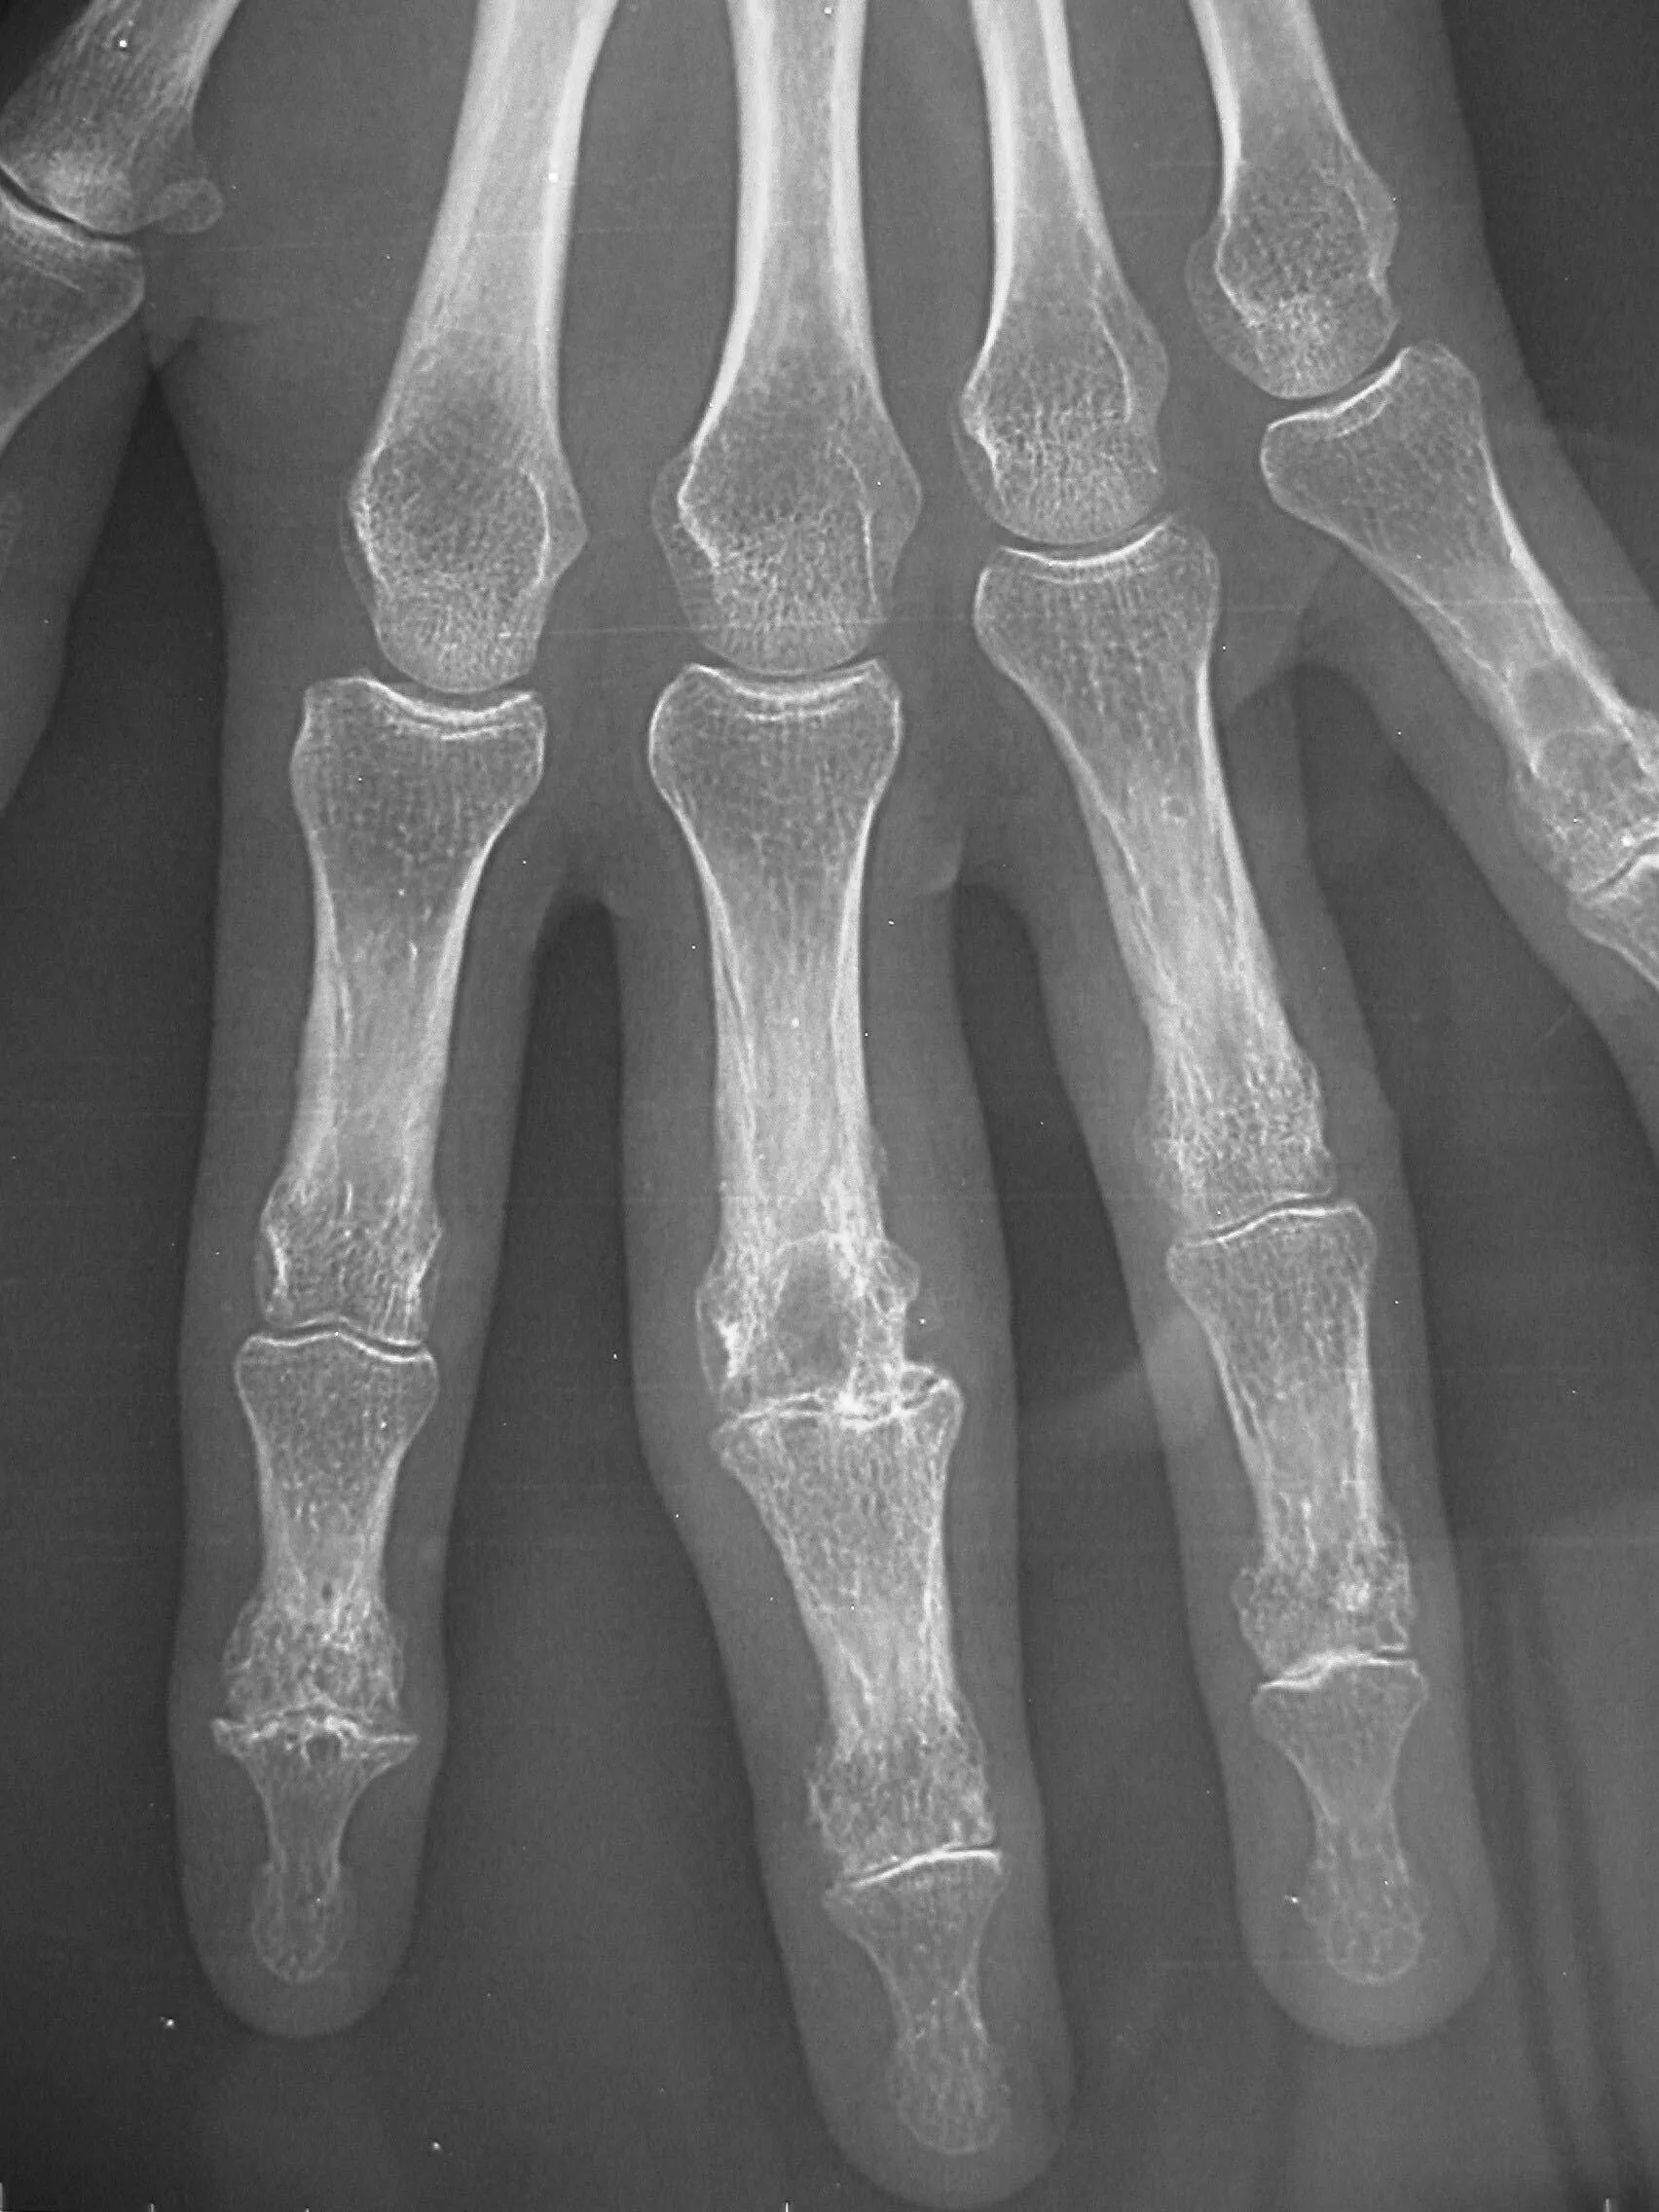

Compilation of hand radiographs from children of different ages (girls on top, boys on bottom) [2] Compilation of hand radiographs from children of different ages (girls on top, boys on bottom)